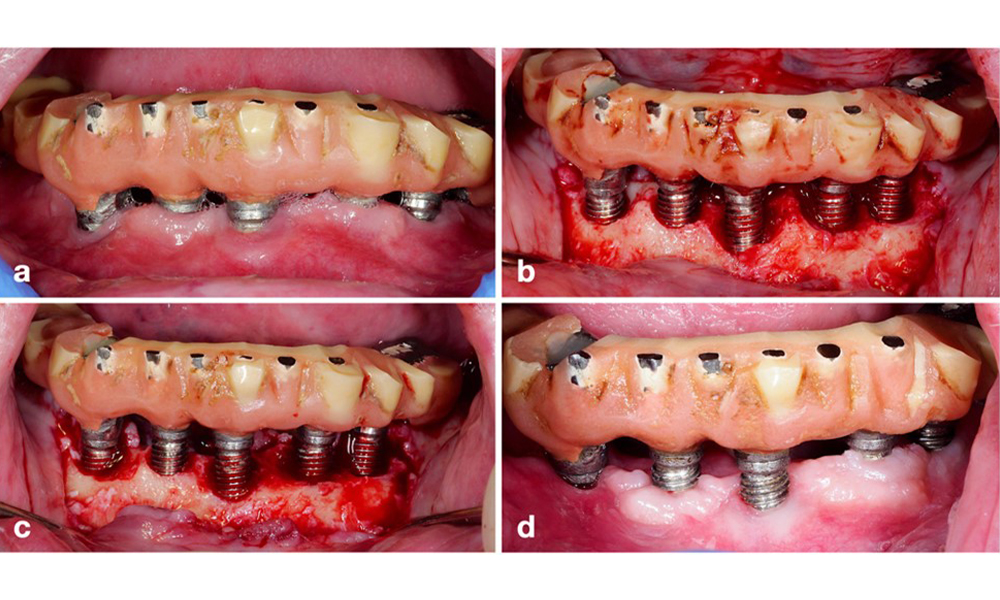

For implants with a modified surface and in regions where bone regeneration is unlikely, implantoplasty should be considered. This procedure involves removing implant threads and smoothing of the micro-structured implant surface with rotating instruments (figure 12). This approach facilitates comprehensive decontamination of the implant surface, and – most importantly – improves postoperative biofilm control (Bertl and Stavropoulus 2021; El Chaar et al. 2020; Geremias et al. 2017). Due to a lack of sufficient clinical evidence there is controversy about the role of implantoplasty (Herrera et al. 2023; Ramanauskaite et al. 2021), however the concerns about inducing inflammation by the inevitable deposition of titanium particles and the increased risk of implant fracture due to reduction of implant strength have not been substantiated (Stavropoulos et al. 2019).